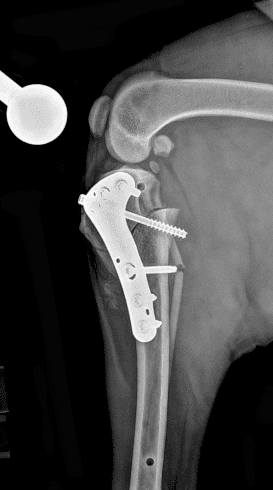

정형외과 전공의 수의사가 직접 수술합니다.

12정교한 정형외과 도구를 사용하여 신속 정확한 정형외과 수술이 가능

13수술 중 골절 상태 혹은 이식물 적용 후 상태 등 육안으로 명확히 확인하기 힘든 상태를 X-ray 확인하여 정확한 수술 결과를 만들어 내는 것이 가능